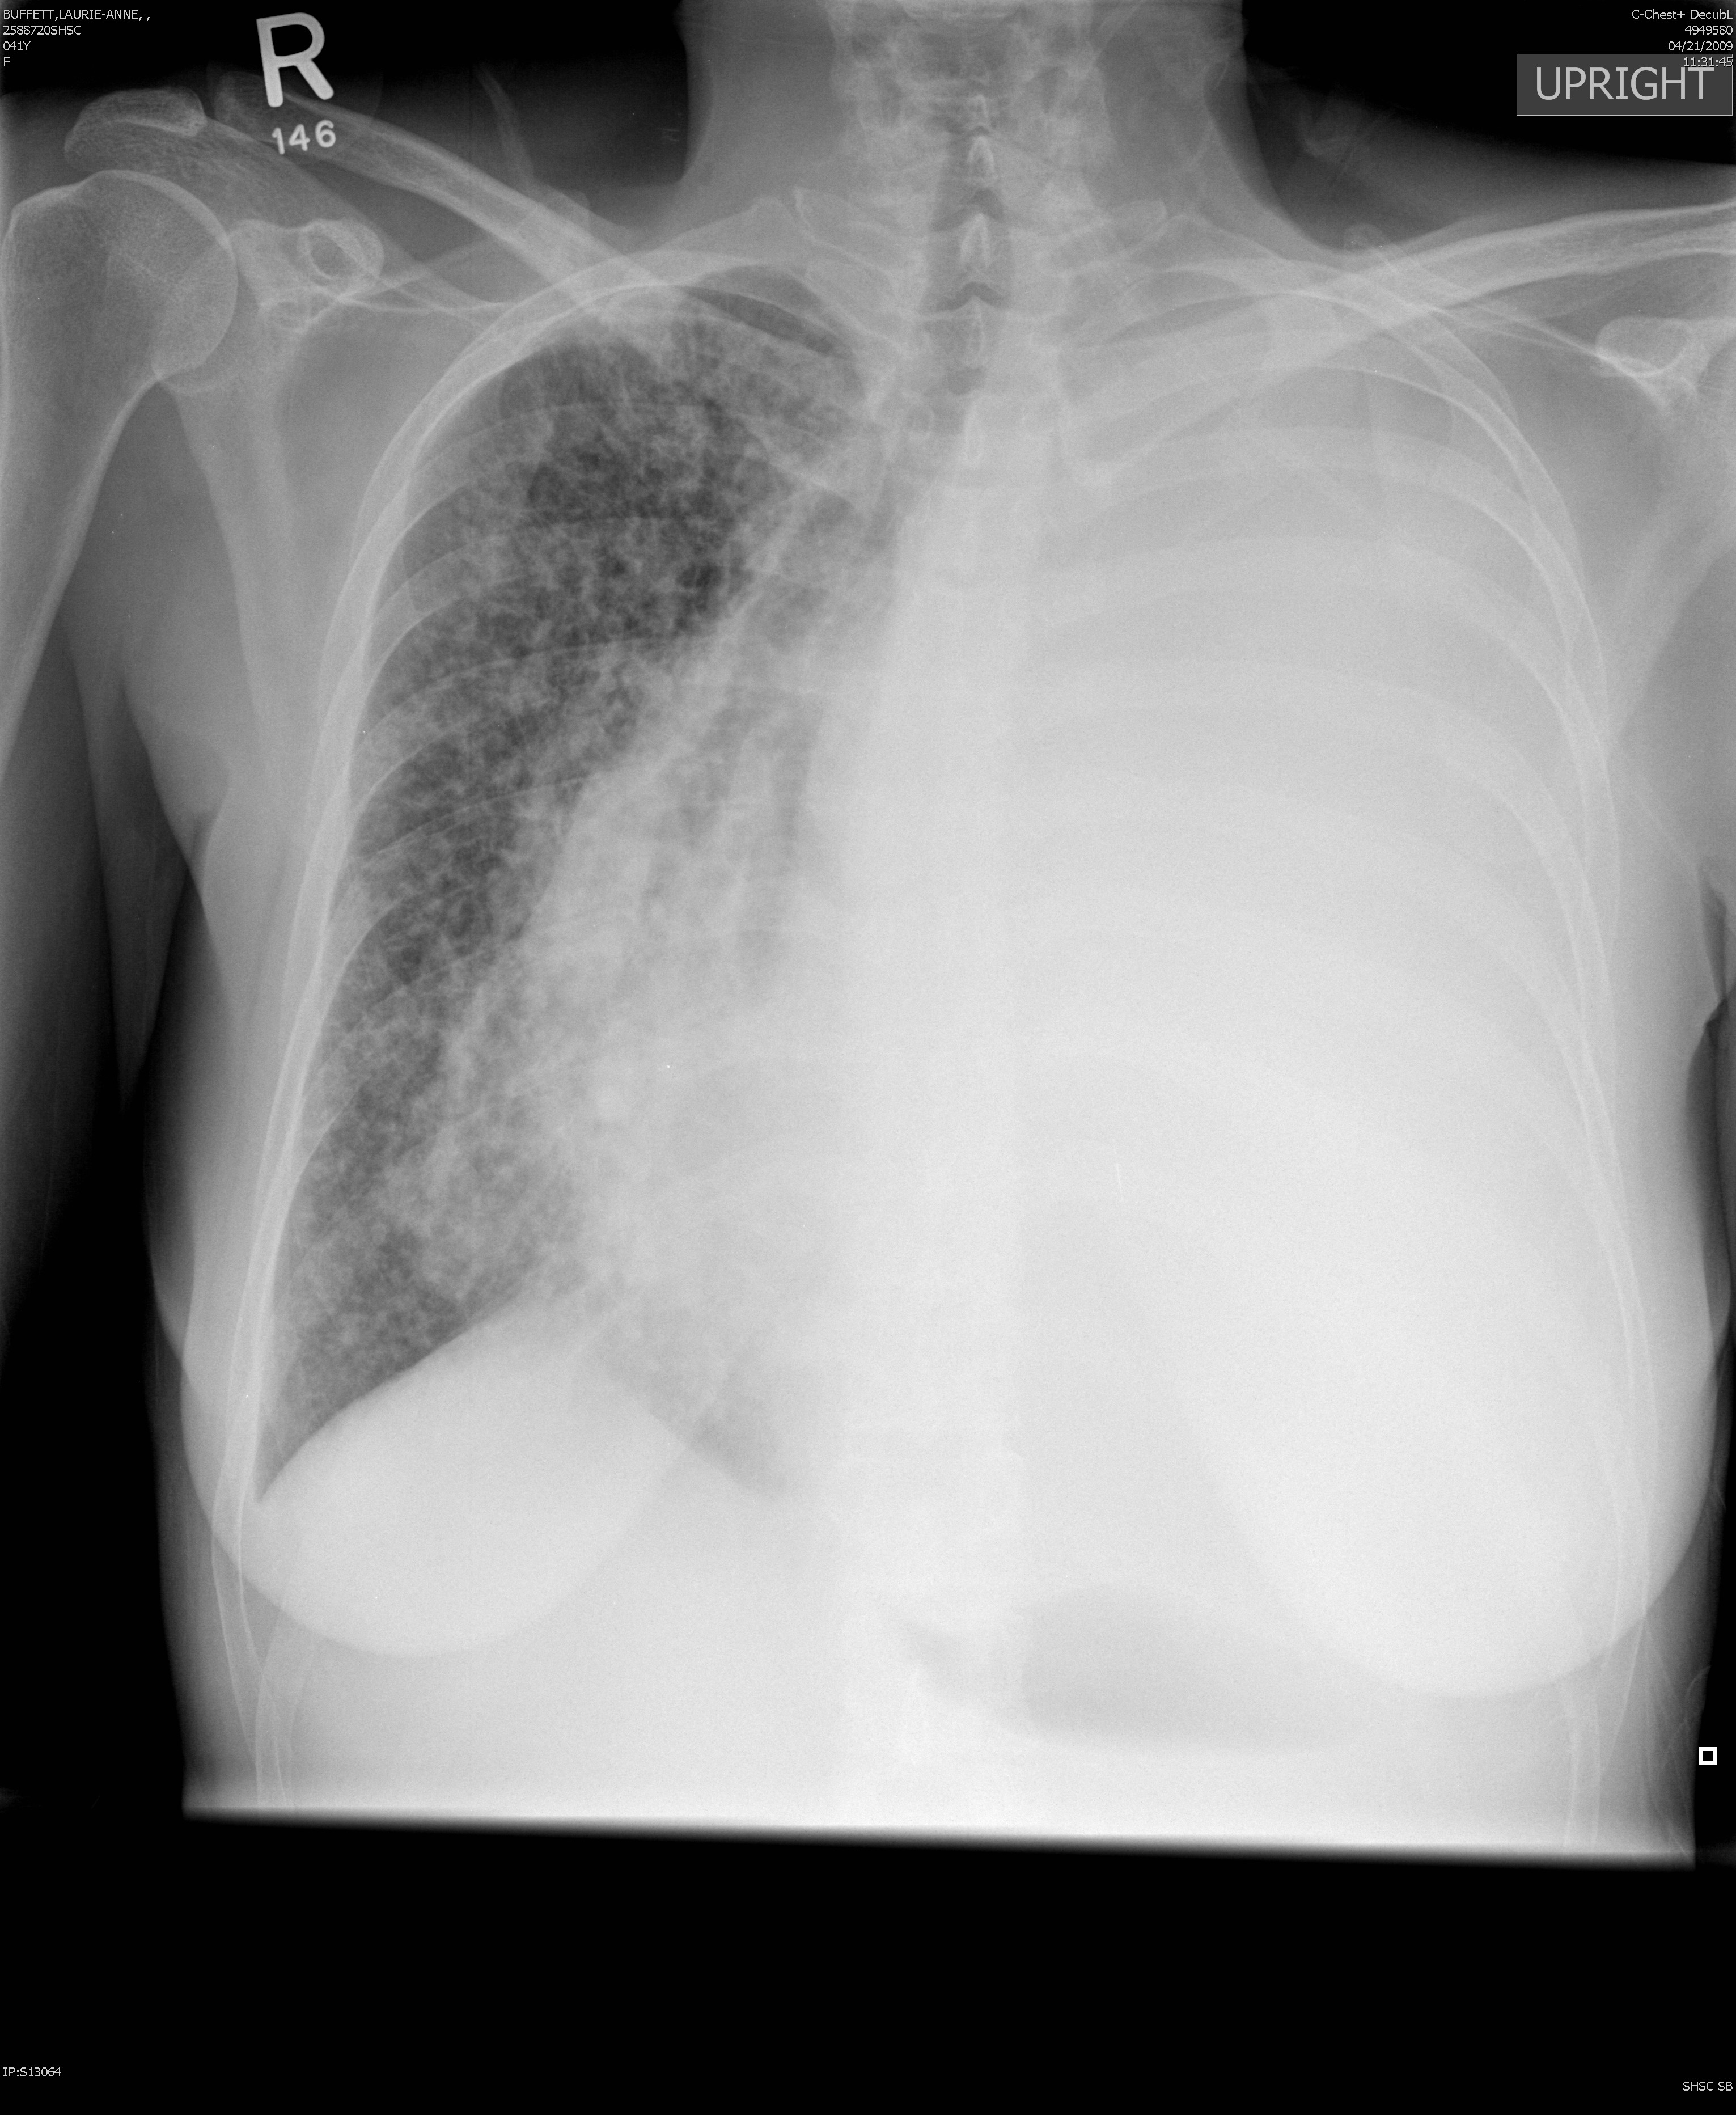

Lung Cancer